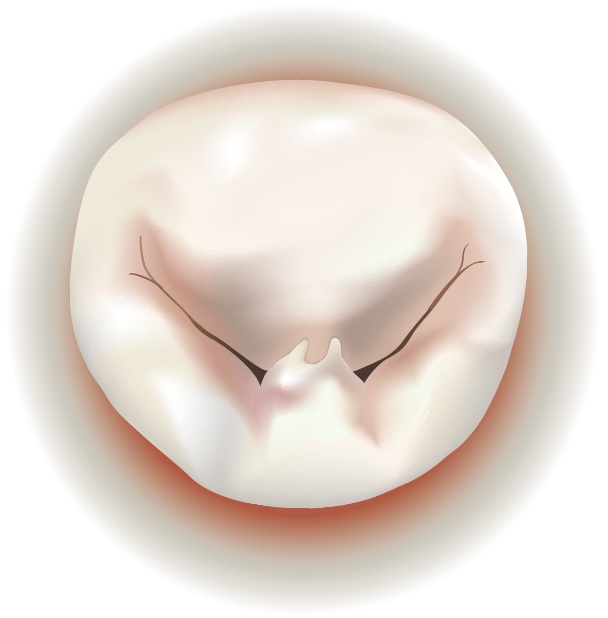

Degenerative mitral valve disease is a common disorder affecting around 2% of the population. Common findings include a “prolapse” ( slipping or falling our of place), due to elongation or rupture of the chordal apparatus. When the two leaflets fail to close tightly, the mitral valve becomes insufficient, sometimes allowing blood to leak back into the atrium from the ventricle.

A prolapse can occur on either the anterior (front) leaflet or the posterior (rear) leaflet. Usually, the annulus, where the leaflets attach, is also dilated or enlarged.

| Mitral Valve Prolapse on Anterior Leaflet | Mitral Valve Prolapse on Posterior Leaflet |